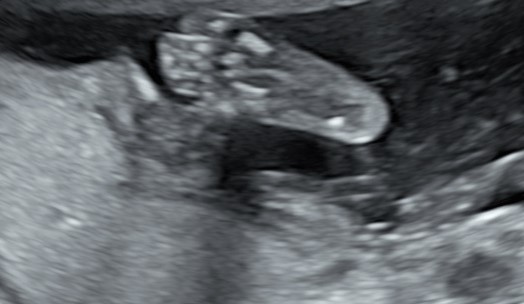

L’ecografia morfologica, come tutte le ecografie ostetriche, deve dare ampio spazio anche ai genitori, alle loro curiosità, al loro bisogno di essere rassicurati, ed è da questa settimana che si possono fare delle bellissime foto in 2D e 3D del volto del piccolo, sia frontalmente che di profilo, innescando invariabili conflitti sulle presunte somiglianze. Se non abbiamo eseguito l’ecografia pre-morfologica, è questo il momento in cui finalmente abbiamo la conferma se il piccolo è une “tesorino” (sinistra) oppure una “tesorina” (destra).